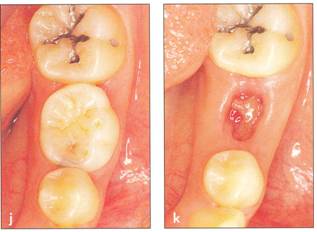

Fi 545e45f g 5-1f After extraction offirst molar from the recipient site. Fi 545e45f g 5-1 g The donor tooth. Note the adequate root form and amount of periodontal ligament on the root. Fi 545e45f g 5-1 h Measurement of the mesiodistal width of the donor tooth. |

Fi 545e45f g 5-1 i Measurement of the mesiodistal width of the recipient site. If the mesiodistal width of the donor tooth is greater than that of the recipient site, the proximal walls of the adjacent teeth are reduced to fit the donor tooth. Fi 545e45f g 5-1j Preparation of the recipient site. Removal of alveolar septum is done with a minirongeur. Fi 545e45f g 5-1 k After removal of the alveolar septum. |

Fi 545e45f g 5-10 Stabilization of the donor tooth. The donor tooth has been splinted to the adjacent tooth with twisted wire and selfcured composite resin after etching and bonding. Fi 545e45f g 5-1 p After transplantation. |